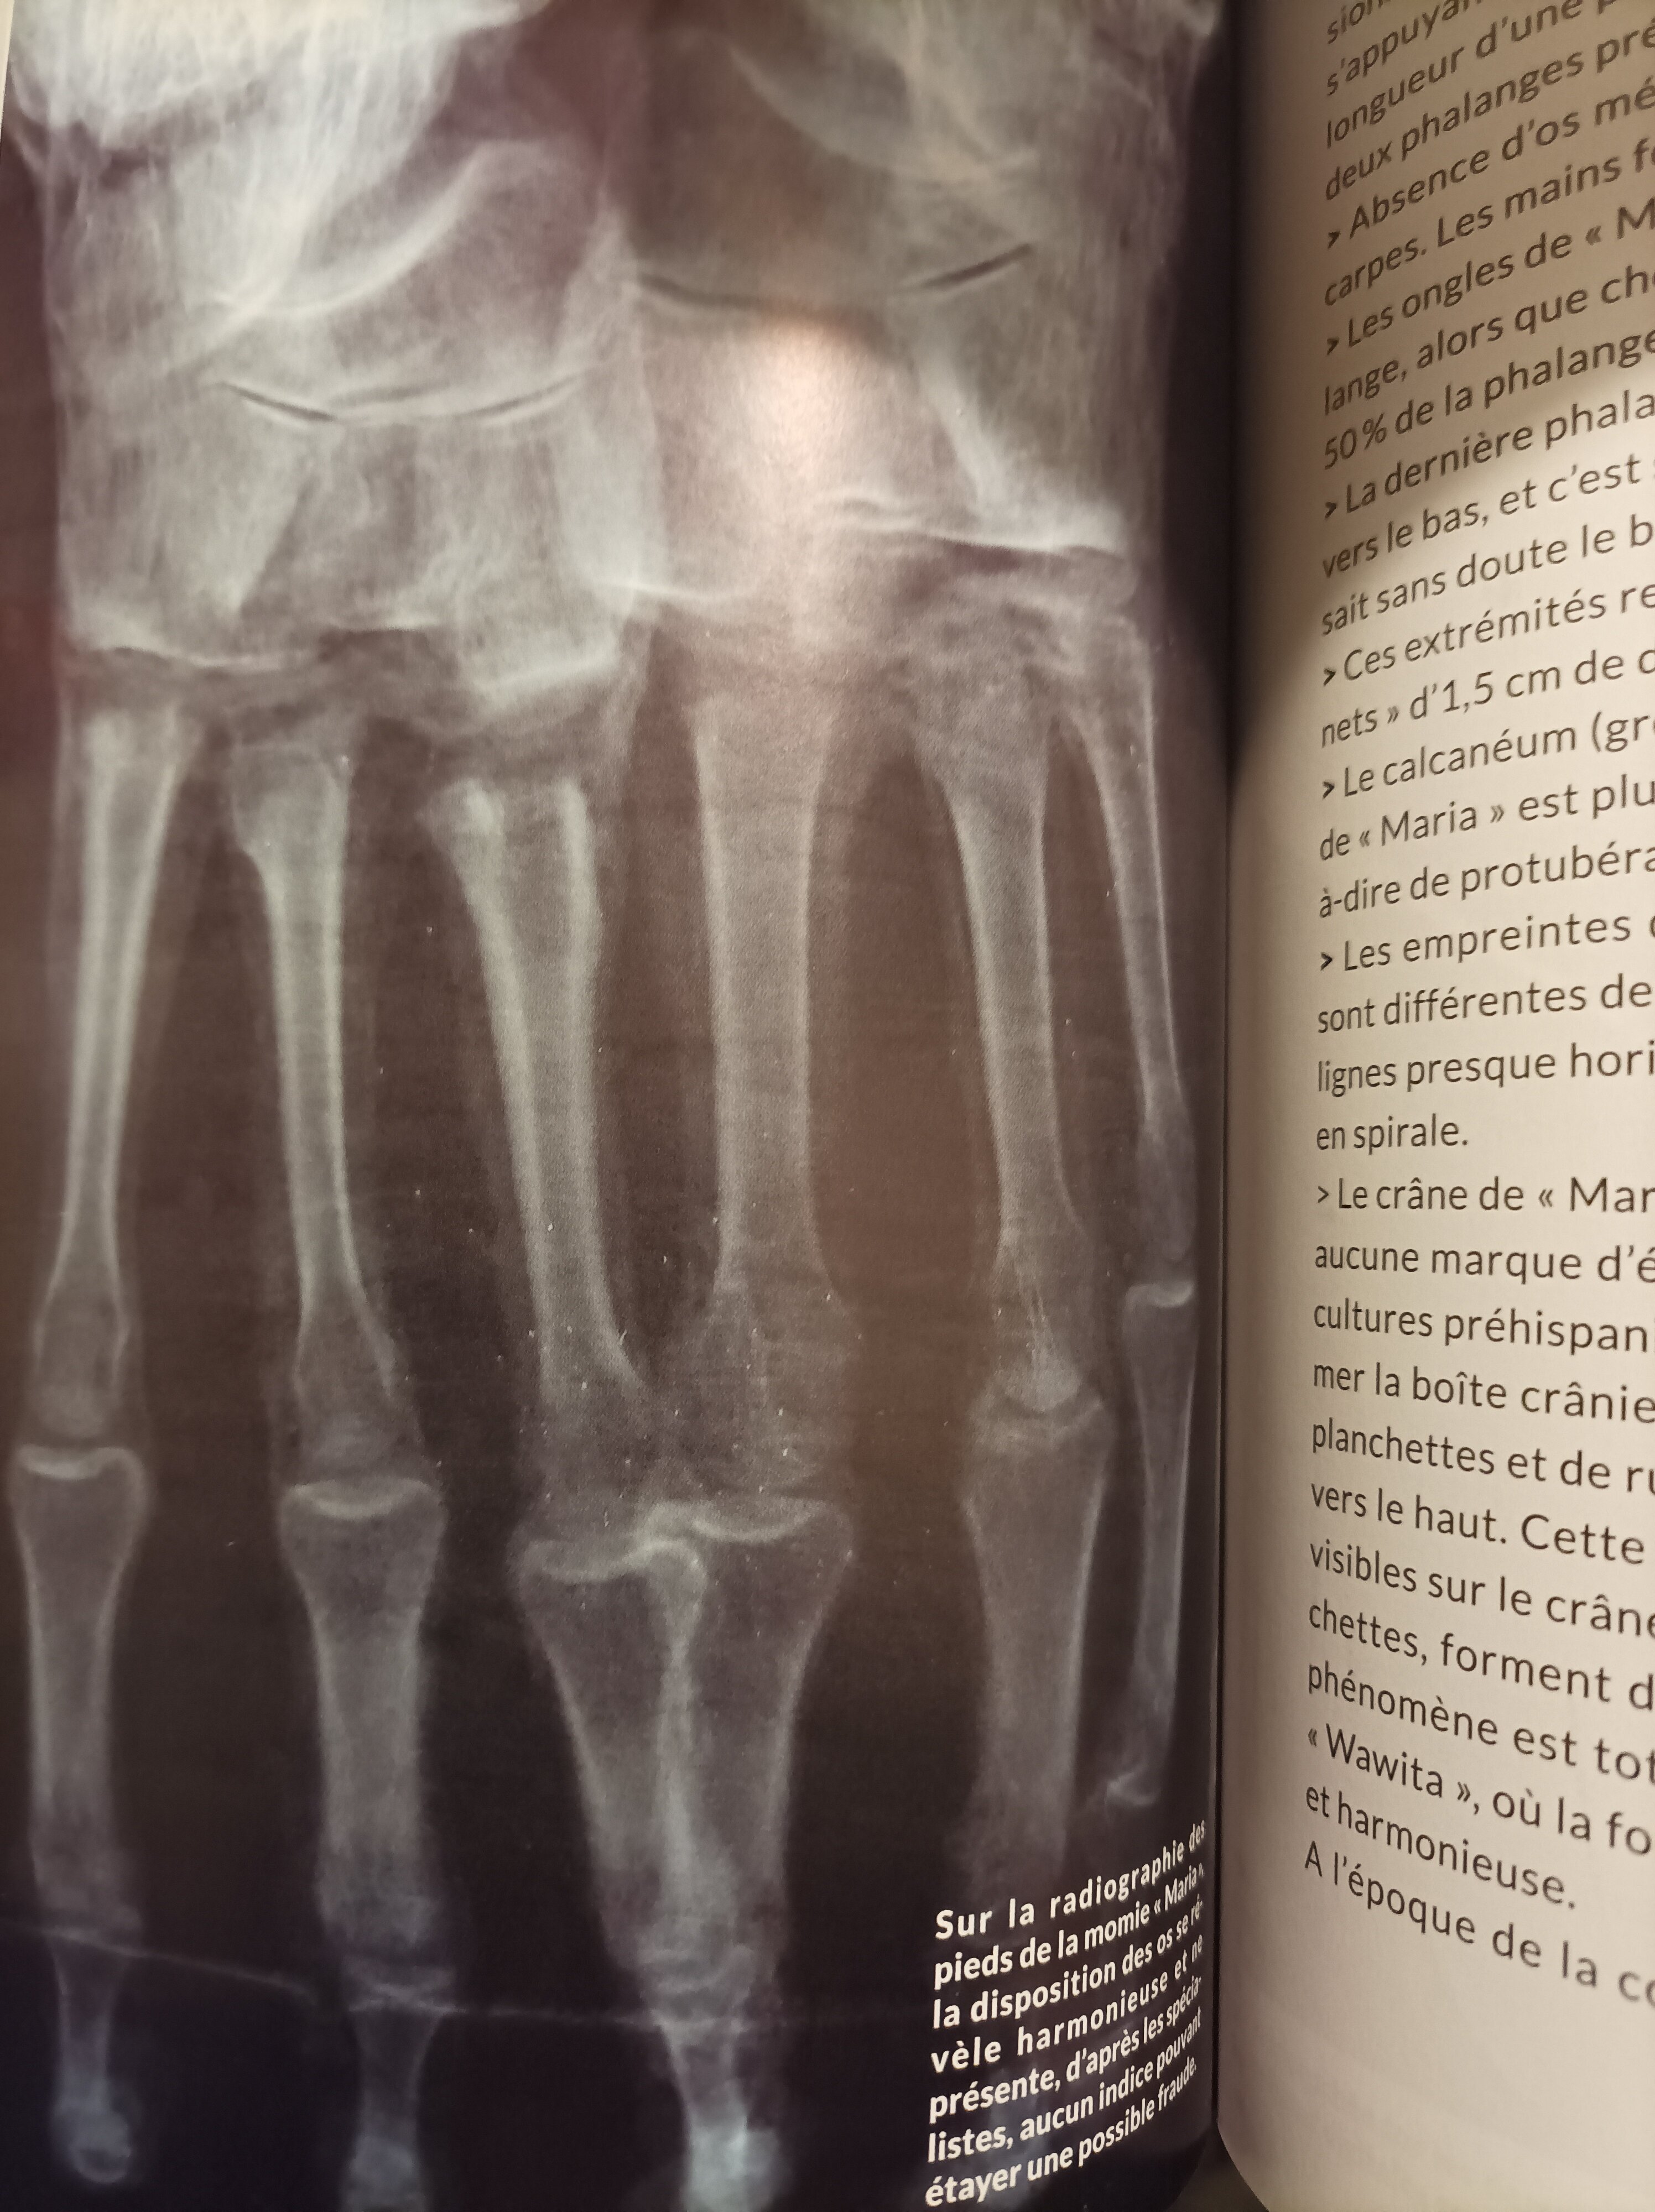

A propos des momies de Nazca, le travail d'analyse effectué sur les corps est sérieux.

Je vous partage quelques photos du livre qui retrace toute l'affaire